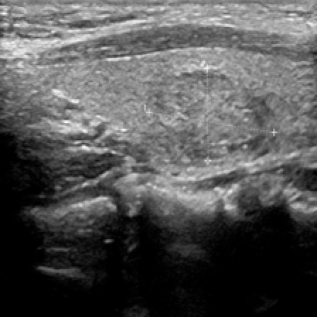

We propose a novel approach that adapts hierarchical vision foundation models for real-time ultrasound image segmentation. Existing ultrasound segmentation methods often struggle with adaptability to new tasks, relying on costly manual annotations, while real-time approaches generally fail to match state-of-the-art performance. To overcome these limitations, we introduce an adaptive framework that leverages the vision foundation model Hiera to extract multi-scale features, interleaved with DINOv2 representations to enhance visual expressiveness. These enriched features are then decoded to produce precise and robust segmentation. We conduct extensive evaluations on six public datasets and one in-house dataset, covering both cardiac and thyroid ultrasound segmentation. Experiments show that our approach outperforms state-of-the-art methods across multiple datasets and excels with limited supervision, surpassing nnUNet by over 20\% on average in the 1\% and 10\% data settings. Our method achieves $\sim$77 FPS inference speed with TensorRT on a single GPU, enabling real-time clinical applications.